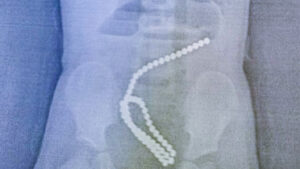

Девочку, проглотившую 60 магнитов, спасли в Комсомольске

Детские хирурги Горбольницы №7 спасли ребёнка, проглотившего магниты. Родители обратились к медикам, когда их двухлетняя дочь стала жаловаться на […]